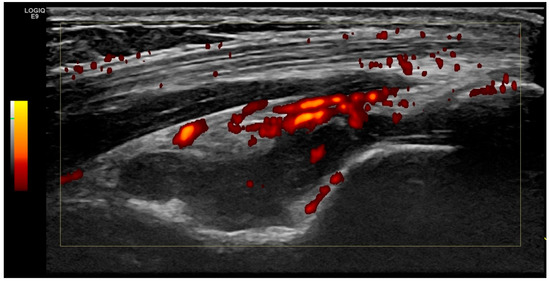

2.2. Ultrasound Examination

2.4. Definition of Elbow Joint Arthritis and Enthesitis

| Hypervascularisation | 4 (3.90 %) | 3 (2.90 %) | 0 (0.00%) | 0 (0.00%) | 0 (0.00%) | 0 (0.00%) |

| Ultrasound arthritis definition (Effusion ≥Grade 2 and/or hypervascularisation) | 27 (26.47%) (grade > II: 25, hypervascularisation: 2) | 25 (24.51) (grade >II: 24, hypervascularisation: 1) | 16 (15.68%) | 0 (0%) | 0 (0.00%) | 0 (0.00%) |